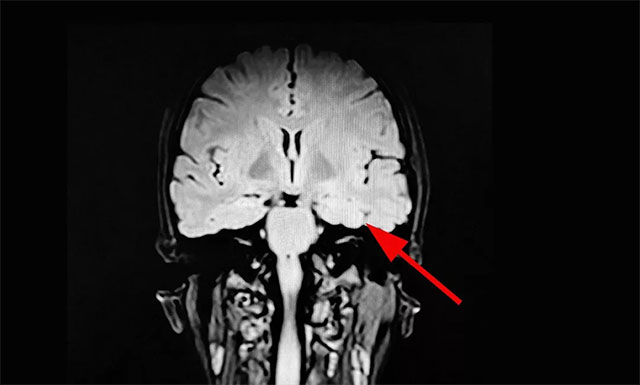

▲ 綜合多種檢查,最終確定患者癲癇病灶

經(jīng)過系列檢查,玲玲被確診為難治性癲癇,系統(tǒng)內(nèi)科藥物治療不佳,影像學(xué)、24小時(shí)長(zhǎng)程視頻腦電監(jiān)測(cè)并結(jié)合患者臨床病史最終定位致癲灶,手術(shù)指征明確,未見明顯手術(shù)禁忌。在征得家屬同意后,楊忠旭教授在助手杜立功協(xié)助下以及崔麗華主任腦電監(jiān)測(cè)輔助下成功為患者進(jìn)行了手術(shù)。目前玲玲已康復(fù)出院。